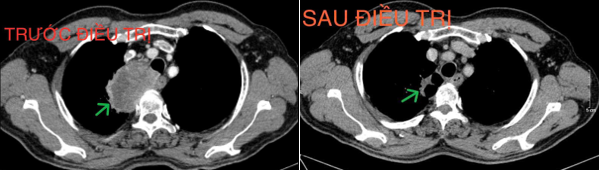

+ Chụp cắt lớp vi tính lồng ngực (16/12/2024): Hình ảnh cấu trúc dạng hang thùy trên phổi phải, kích thước ~36x22x44mm, bờ không đều, thành dày không đều, ngấm thuốc không đồng nhất sau tiêm. Hạch trung thất và rốn phổi phải.

Hình 6. Khối u trước và sau điều trị (mũi tên xanh), sau điều trị kích thước khối u giảm còn khoảng 36x22x44mm

Hình 7. Hạch trung thất trước và sau điều trị (mũi tên xanh), kích thước hạch sau điều trị giảm xuống còn dưới 10mm đường kính trục ngắn.

*Kết luận: Ca lâm sàng trên cho thấy một trường hợp bệnh nhân nam lớn tuổi, chỉ số toàn trạng (Performance Status - PS) 1, vào viện với tình trạng khó thở và đau ngực nhiều, được chẩn đoán Ung thư phổi không tế bào nhỏ giai đoạn IIIB. Sau 4 chu kỳ hóa trị liệu với phác đồ Docetaxel - Carboplatin, bệnh nhân đạt được đáp ứng bệnh một phần, khối u giảm khoảng 50% kích thước so với trước khi điều trị, kích thước hạch trung thất giảm và nhiều hạch không còn nhìn thấy trên phim chụp cắt lớp vi tính. Sau điều trị bệnh nhân hết các triệu chứng lâm sàng, thể trạng được cải thiện và sinh hoạt trở lại bình thường. Bệnh nhân tiếp tục được đánh giá lên kế hoạch điều trị tiếp theo.